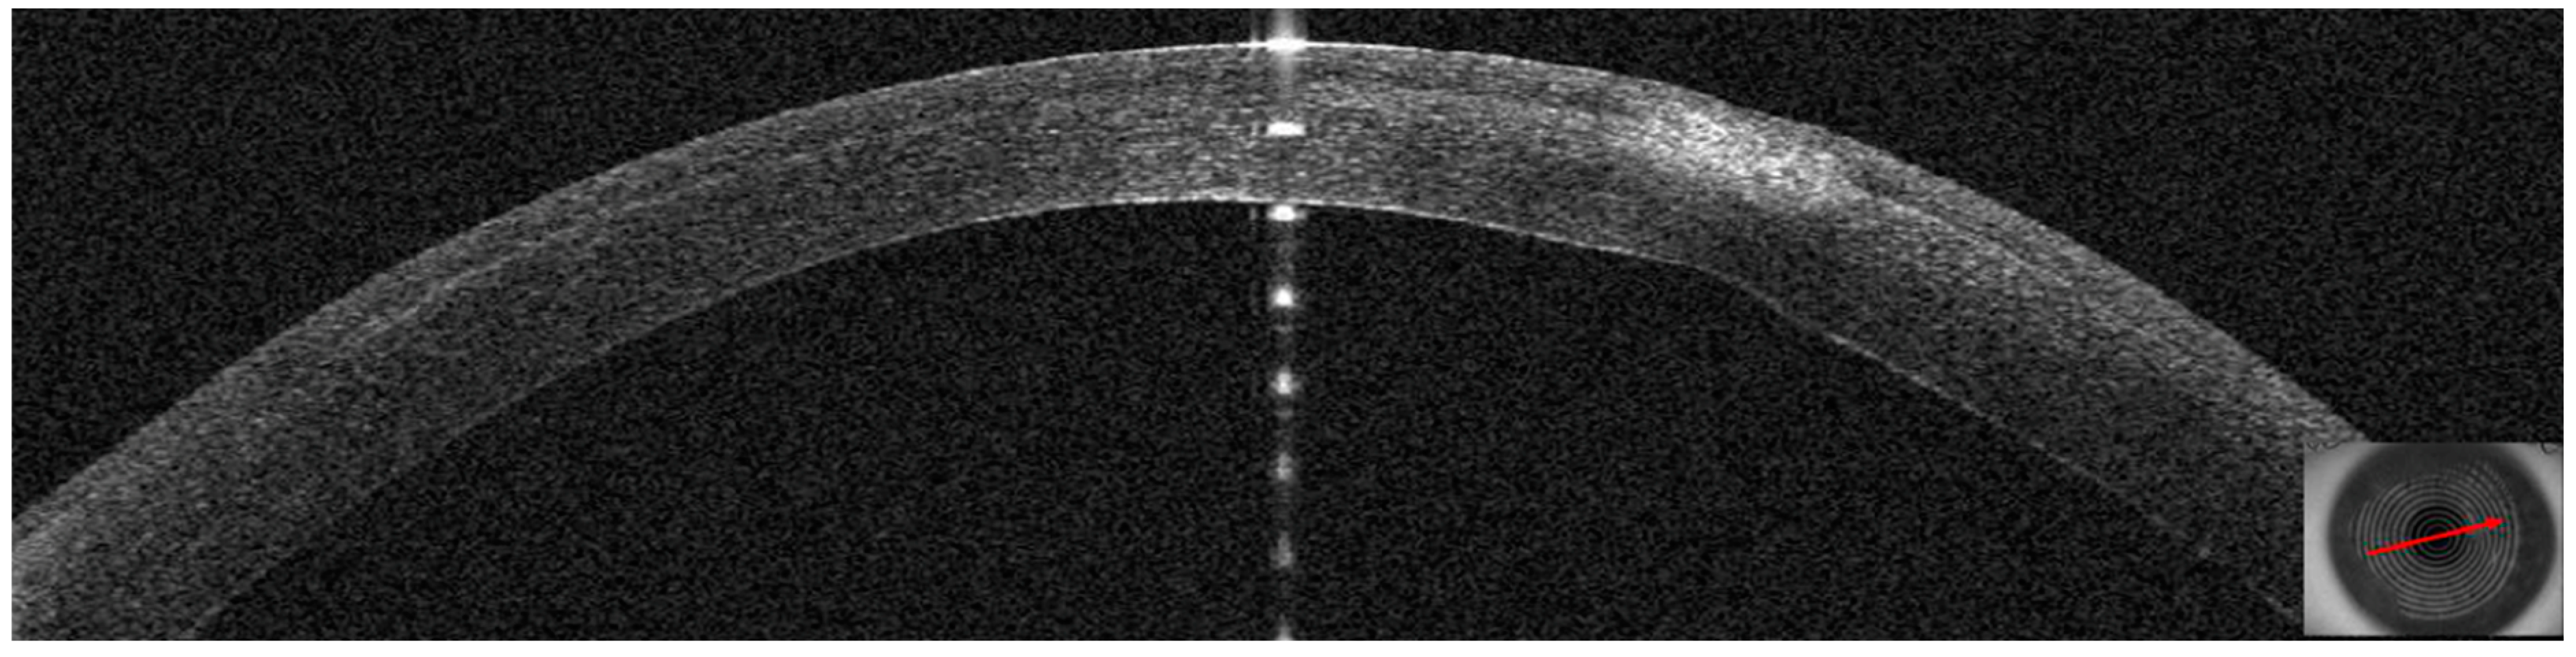

3.4. Patient #4